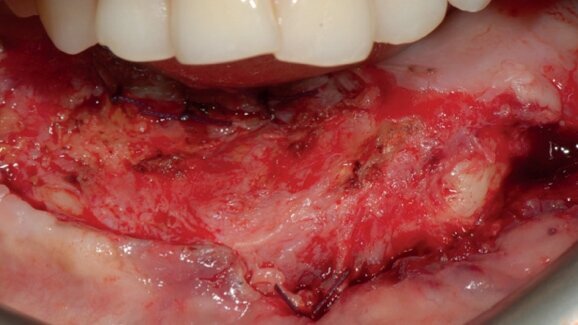

This study was designed as a pilot case series study. At least six months after reconstruction with a fibula free flap, all crestal soft tissue, including skin and muscle, was removed, leaving only periosteum attached to the reconstructed alveolar crest. The soft tissue was then remodeled according to a new technique. One month after complete soft-tissue healing, implants were inserted with a flapless technique using a computer-guided template. Three to six months later, a screw-retained prosthesis was delivered. Outcome measures were implant survival and periimplant mucosal response, based on probing pocket depth (PPD) and bleeding on probing (BOP).

Six patients (four males and two females) with a mean age of 48.4 years were treated. A total of 32 implants were inserted. No dropout occurred during the entire follow-up period. No implant failed and the overall implant survival rate was 100% 12 months after definitive prosthesis delivery. All of the patients presented with healthy soft tissue, stable PPD and good BOP values at the one-year follow-up. The mean PPD values were 3.6 ± 0.6 mm and the mean BOP values were 9 ± 4.8%.